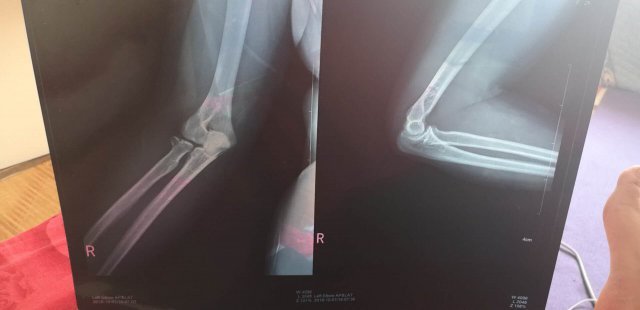

但是回家后疼痛并未减轻,10 月 2 日崔女士来到医院检查为双侧桡骨小头骨折,右手更是粉碎性骨折,至今无法动弹。崔女士介绍,这是她在赛奥健身上的第三节课。